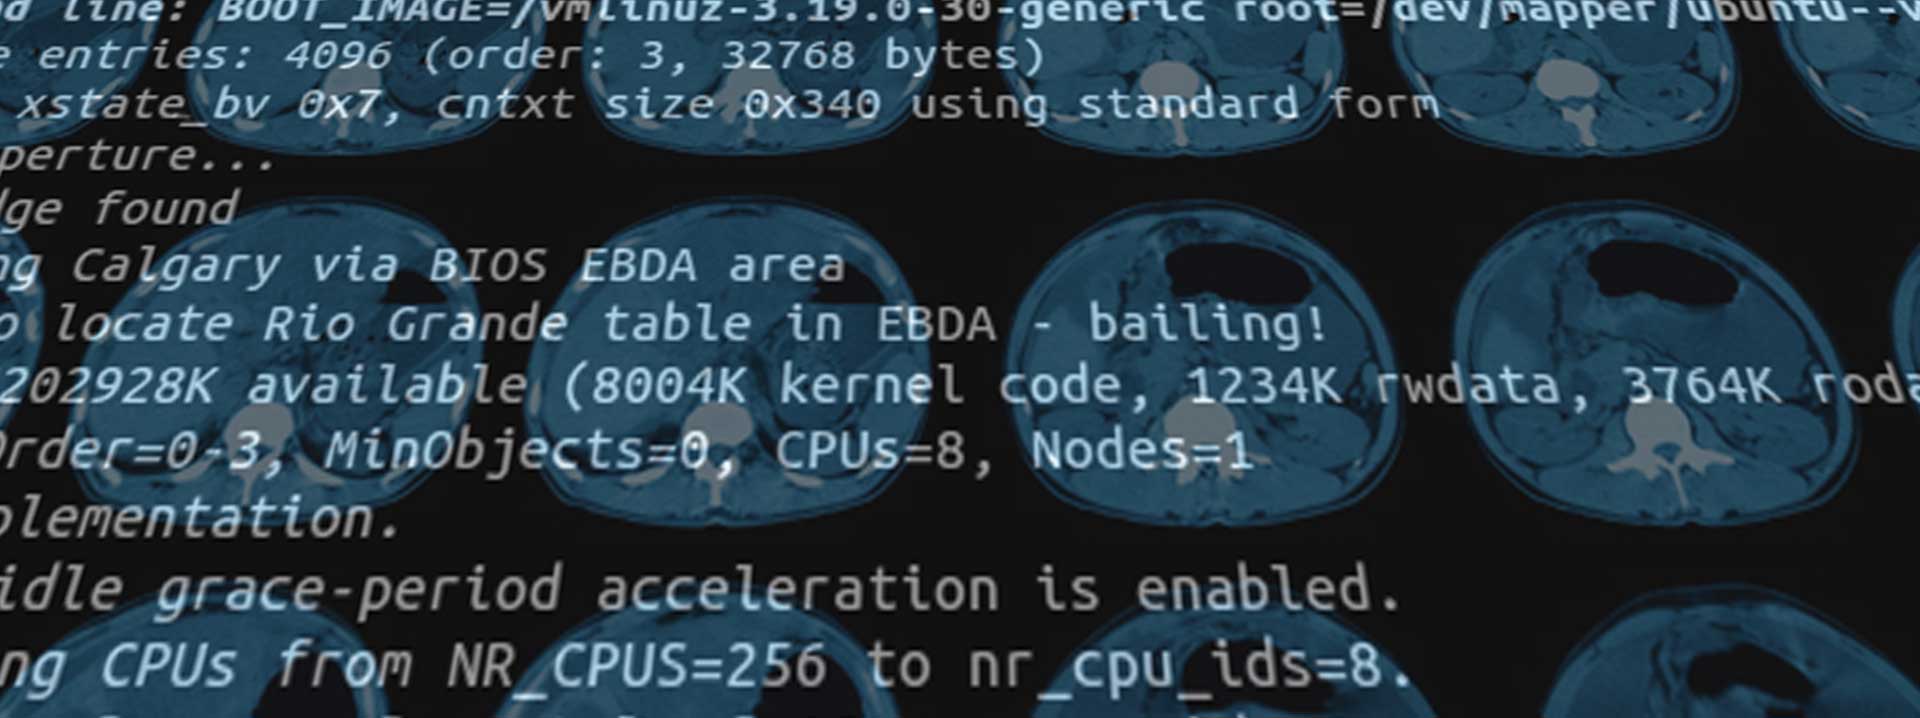

Our company was found in 2009 and targeting AI application development in the region. We united groups of IT professionals and business analysts to develop AI apps in medical imaging analysis.

Deep Learning is a innovating technology in artificial intelligence which enables automatic lesion detection, classification and segmentation in medical images in unprecedented efficient way.

By using our AI apps, medical doctors can get diagnostic results with highlighted lesion areas in just couples of minutes.

With significant increase in productivity, we can now focus on abnormalities and provide better treatments for the patients.